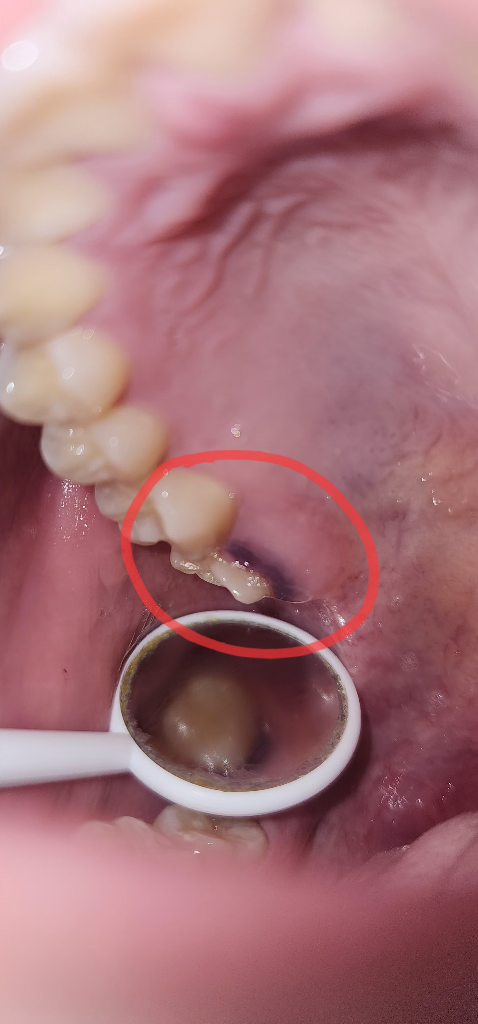

자연적으로 치료가 될 가능성이 높아보이는 소견으로 관련하여서는 경과룰 지켜보시길 권고드립니다. 만약 시간이 경과하여도 좋아지지 않는다면 그 때에 이비인후과적으로 치료를 받아보아도 문제될 것은 없어 보입니다.

안녕하세요. 장우영 의사입니다.

부풀어 오른것은 시간이 지나면 서서히 나을겁니다

시간은 많이 걸릴거에요 속에 피가 난것이 서서히 흡수되서 처리 되거든요 그런데 마지막 어금니 상태가 별로 인걸로 보이네요 -_-;;;

치과 검진을 받아보세요